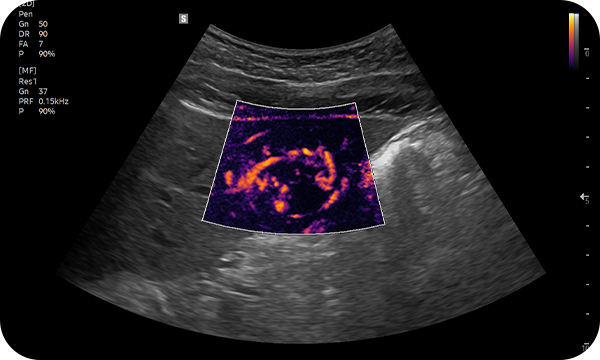

MV-Flow™ isualiza el flujo sanguíneo microcirculatorio y lento para mostrar la intensidad en color. Este modo es adecuado para observar el flujo sanguíneo microcirculatorio y el volumen de flujo sanguíneo lento.